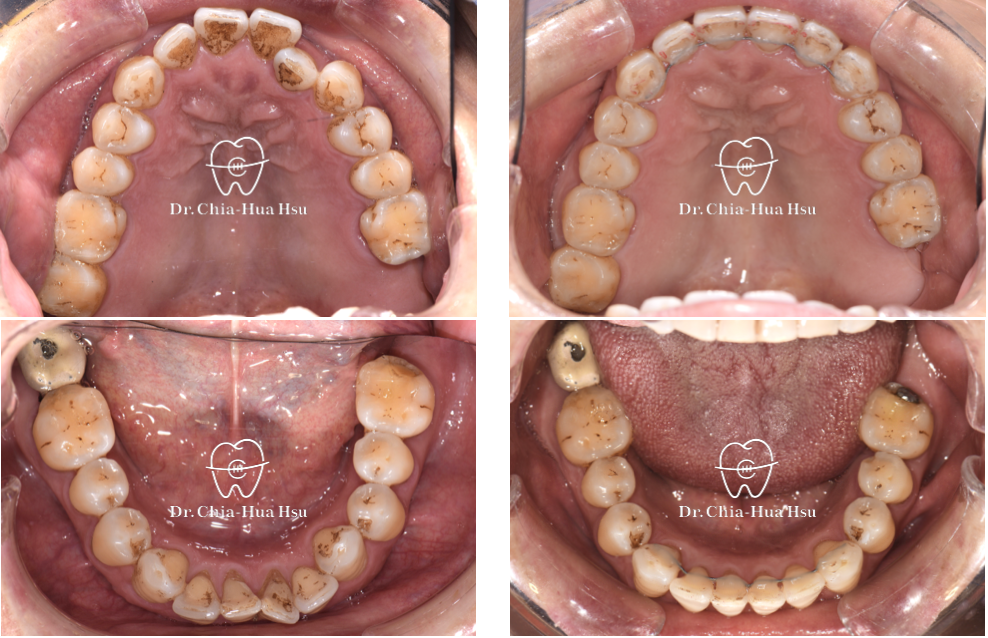

治療前

治療後

治療前

治療後